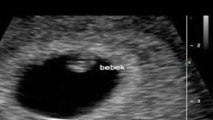

Gebelik sürecinde dikkat edilmesi gerekenler nelerdir?

Kadın Hastalıkları Doğum ve Tüp Bebek Uzmanı Op. Dr. Seval Taşdemir, gebelik sürecinde dikkat edilmesi gerekenleri anlattı.